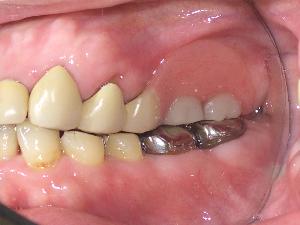

部分入れ歯は何本かの歯が連なって失われてしまった場合に作成します。部分的な入れ歯です。床(しょう)という土台の上にバネではなくと自分の歯を使用して固定します。 |